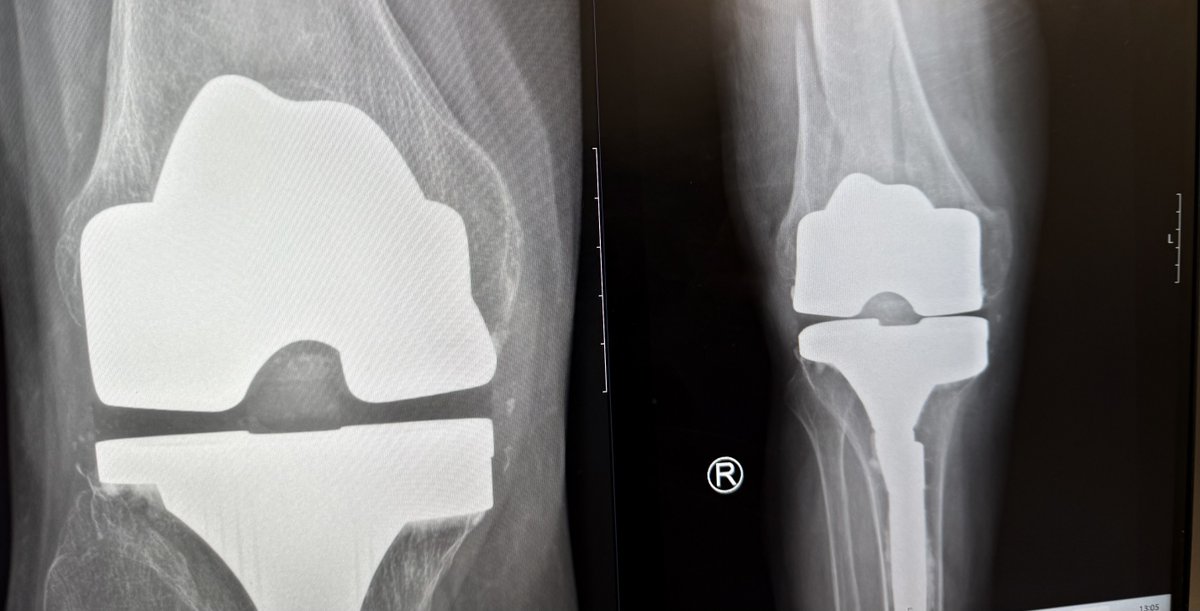

Fix or replace has been the question for distal femur fractures. But what happens when the fixation fails?

This systematic review compares:

• Primary DFR

• Salvage replacement after failed fixation